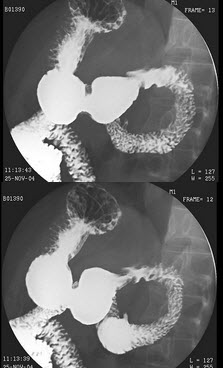

12、单项选择题

女,39岁,左下肺叶切除术后。体检:左下肺呼吸音弱,行胸腔闭式引流术,引流出脓性分泌物。结合图像,最可能的诊断为()

A.正常表现

B.会厌征

C.食管憩室

D.食管溃疡

E.食管下段胸腔瘘

点击查看答案